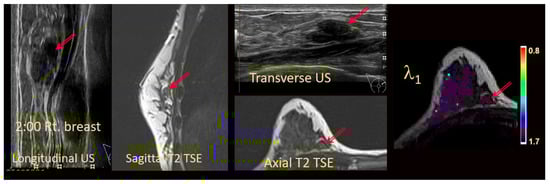

| Lesion visible (2) and all purple. | Definitely benign (Bx = 0) | No biopsy (see Figure 3a) |

| Lesion not visible (0, 1), but there are only purple pixels in area of the lesion (no noise). | Definitely benign (Bx = 0) | No biopsy (see Figure 3b) |

| Lesion not visible (0, 1), but there are colored pixels or noise in the area. | NOT definitely benign (Indeterminate) (Bx = 1) | No change to the existing biopsy recommendation (see Figure 3c) |

| Lesion visible (2) and contains any colored pixels. | NOT definitely benign (Indeterminate) (Bx = 1) | No change to the existing biopsy recommendation |

| Lesion visible (2) and contains many colored pixels with red pixels. | Suspicious (Bx = 2) | Biopsy (see Figure 3d) |